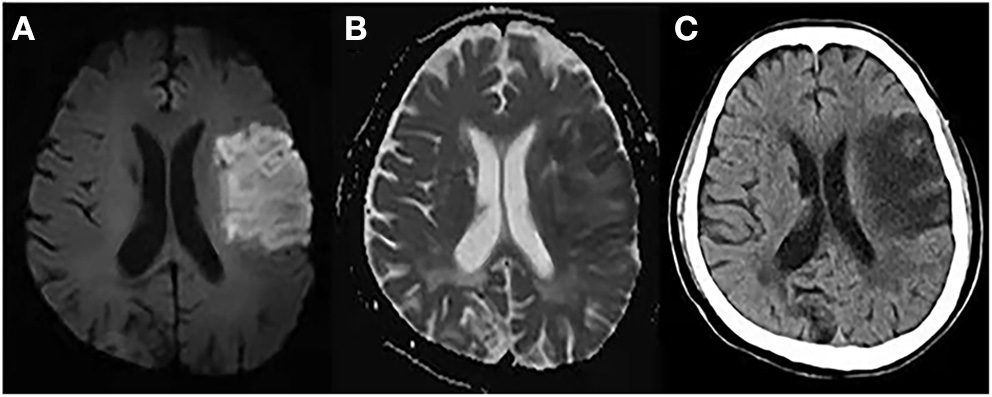

Recent studies have proposed the use of NWU within the lesion area to determine the volume of edema (12, 48–50). NWU is calculated using the equation NWU = 1 – DIschemic/DNormal, where DIschemic (Hounsfield Unit, HU) is the density of the ischemic core with hypoattenuation, and DNormal is the density of the same area in the contralateral normal tissue (21, 49, 51) (Figure 3). This quantitative method is based on a physical principle in which the product between the volume of a body and its mean CT density remains constant, regardless of the volume of water uptake (49). Therefore, the increased water content is proportional to the NWU, and the edematous component of the infarct lesion can be quantified using CT densitometry according to the following equation: edema volume = lesion volume × NWU.

Figure 3

Measurement of % net water uptake (NWU) per volume on admission. (A) The initial ischemic core is identified by the initial relative cerebral blood flow (CBF) volume using a threshold of <30% in CBF maps. (B) Non-enhanced computed tomography shows a slight decrease in the density of the right basal ganglia region. (C) The mean density of the initial core (Dischemic) (red) was calculated in relation to the normal density (Dnormal) (green) in the homotopic contralateral region. NWU = 1 – DIschemic/DNormal.

CT-based NWU quantification has been described as a precise method to determine the individual volume of edema (21). A previous study demonstrated that it is related to histopathological measurements of the volume of water uptake (52). Fu et al. proposed a new image patch-based NWU procedure that only uses non-enhanced admission CT without the need for lesion segmentation (53). However, this approach has other limitations; for example, patients with pre-existing stroke or significant carotid stenosis may have hypodense lesions, which affect NWU measurement.